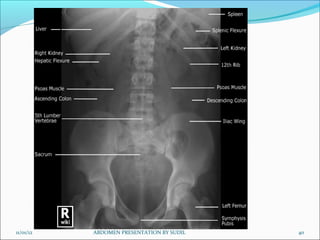

Picture criteria:

 Whole of abdomen from upper abdomen to symphysis pubis.

 Lateral abdominal wall and the properitoneal fat layer.

 Psoas muscle, lower border of liver and the kidneys.

 Ribs and spinous processes of the lumbar vertebra.

 Whole of the urinary tract should be visualized.

 Bowel gas pattern with minimal unsharpness.